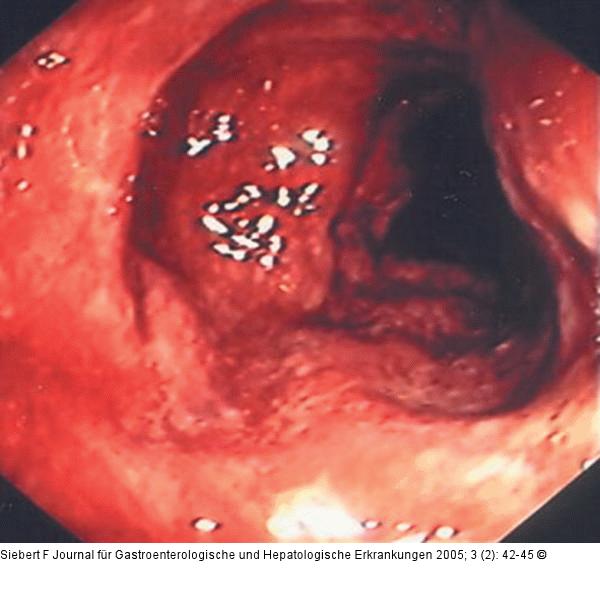

Abbildung 8a-d: Kolon-Ischämie - Differentialdiagnosen Differentialdiagnose Ischämische Colitis (oben) – Colitis ulcerosa (unten) |

Abbildung 8b

Abbildung 8a-d: Kolon-Ischämie - Differentialdiagnosen

Differentialdiagnose Ischämische Colitis (oben) – Colitis ulcerosa (unten) |